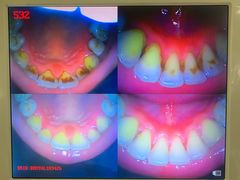

• 土豆口腔(凤凰北总店)

• -土豆口腔(凤凰北总店)

匿名用户 | 22-11-09